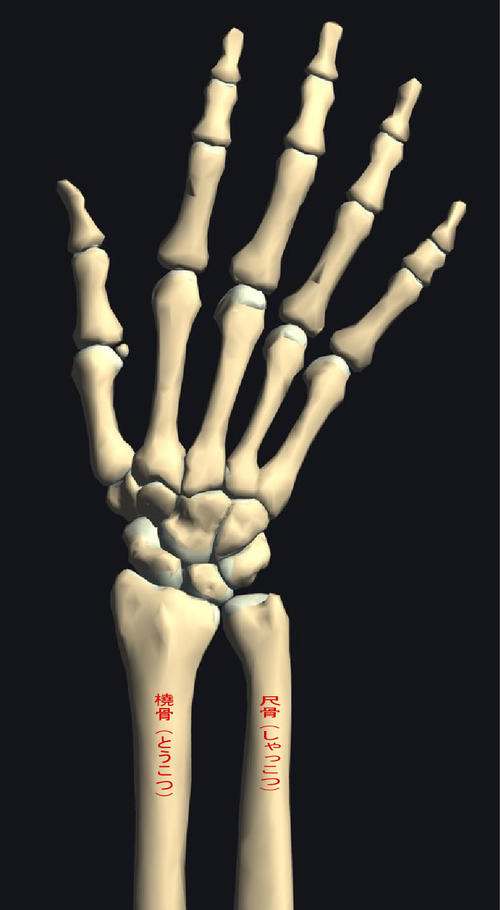

てくび.jpg

「橈骨遠位端部骨折」という骨折です。

手首の骨折は折れ方により、コーレス骨折、スミス骨折、

背側バートン骨折、掌側バートン骨折と分類されています。